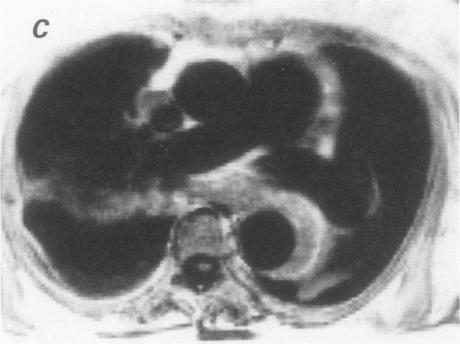

Magnetic resonance imaging is an excellent noninvasive method for evaluating thoracic aortic dissections. A variety of magnetic resonance scans of aortic dissections are shown, documenting the ability of magnetic resonance to image the true lumen, the false channel, and the intimal septum. Detail is provided on magnetic resonance imaging techniques and findings.

磁共振成像是评估胸主动脉夹层的一种出色的非侵入性方法。展示了各种主动脉夹层的磁共振扫描图像,证明了磁共振对真腔、假腔和内膜隔膜成像的能力。文中提供了磁共振成像技术及结果的详细信息。